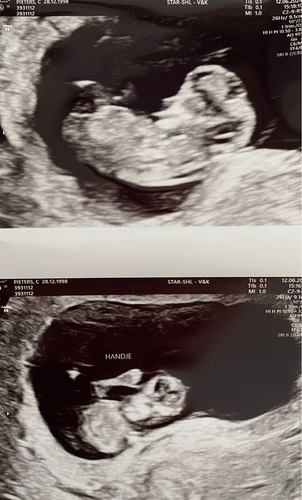

Reactie op carmenpdr

6 januari 馃槏

Hij/zij zwaait naar je!!